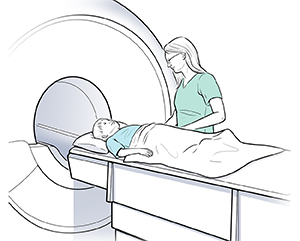

Imaging tests. These may include an MRI or CT scan to check tumor size and location.

| With NF2, your child may have an imaging test, such as an MRI or CT scan, to check for tumors. |